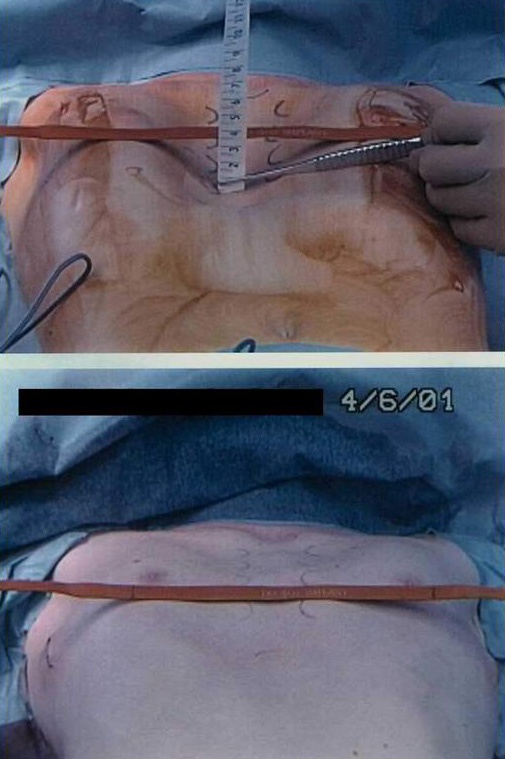

Under general anesthesia, an epidural catheter is placed to aid in perioperative pain control. An endotracheal tube, radial arterial line, and Foley catheter are placed. A sterile marking pen marks the skin at the interspaces of maximal pectus depth on each side of the sternum. The defect usually involves the lower one half to two thirds of the sternum. The deepest point is typically just superior to the junction of the sternal body and the xiphoid process.

The preoperative anatomy is documented with photography in the AP plane (Figure 2) and lateral plane. Eventually, a retrosternal stainless steel bar will be placed from midaxillary line to midaxillary line at the level of maximal pectus depth. The length from midaxillary line to midaxillary line is measured in order to select the proper bar size.

The two incisions, each less than one inch long, are then closed with absorbable monofilament sutures (Figure 15). A chest X-ray is performed in the operating theater to document satisfactory bar position and evaluate for pneumothorax. The post-repair anatomy is documented with photography in the AP plane (Figure 16) and lateral plane. Patients are extubated in the operating theater.